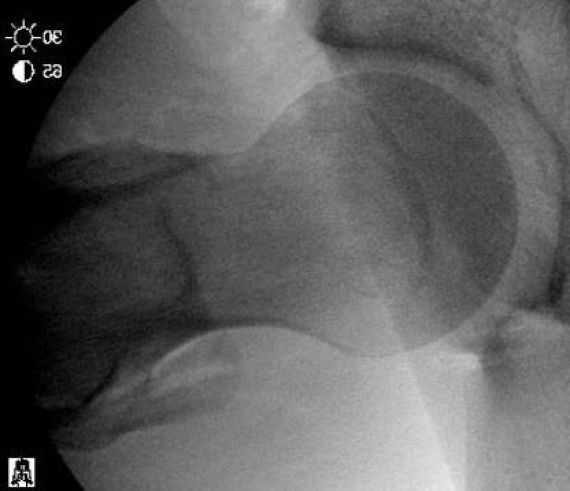

- Femoroacetabular Impingement (FAI) - Cam deformity; Pincer deformity

Hip conditions often improve with conservative treatment including a short course of rest, anti-inflammatory pain medication, and physical therapy. An ultrasound-guided cortisone injection is sometimes necessary for patients with persistent pain. If pain continues despite conservative treatment, hip arthroscopy is an excellent treatment option for patients with labral tears, femoroacetabular impingement (FAI), tears of the gluteus medius or proximal hamstring, among other conditions.